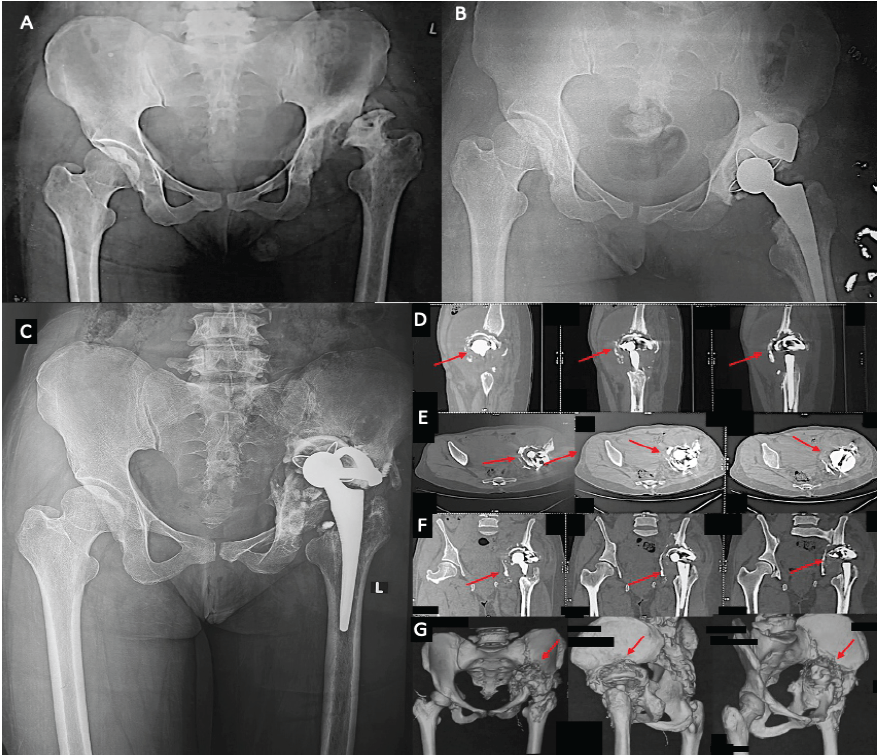

A 36-year-old female, with a history of left THR performed 4 years earlier, presented with progressively worsening left hip pain and difficulty ambulating for 8 months following a fall. The pain was insidious in onset, localized to the left hip, aggravated by prolonged standing and walking, and relieved by rest. She had no significant medical comorbidities. Her initial presentation 4 years prior had included similar hip pain, limb shortening, and restricted range of motion. She also reported a childhood limp secondary to trauma at age 12. Radiographs at that time demonstrated a deformed, fragmented femoral head; a shallow, arthritic acetabulum; and the presence of a pseudo-acetabulum. She subsequently underwent a left THR in which a metal augment was used to address the superolateral acetabular deficiency, and serial reaming was performed to accommodate the shallow acetabular morphology. Her post-operative course was uneventful, with 6 months of supported rehabilitation. At the current visit, examination revealed a bipedal assisted Trendelenburg gait, global restriction of painful hip movements, anterior and posterior joint line tenderness, and a limb length discrepancy. Radiographs showed superior migration and protrusion of the acetabular component, fracture of the anchoring screws of the metal augment, and lateral displacement of the augment. Computed tomography (CT) scan with 3D reconstruction using metal artifact reduction system (MARS) further confirmed implant failure, demonstrating extensive superolateral and acetabular bone loss (Fig. 1).

Figure 1: (a) The pre-operative radiograph before the primary total hip replacement (THR) (first contact) and image, (b) the post-operative primary THR with a metal augment fixation. (c) The radiograph after re-occurrence of symptoms showing implant failure with screw breakage and migration supero-laterally. (d-g) The computed tomography images with three-dimensional reconstruction, showing the bony defects in acetabulum and pelvis.